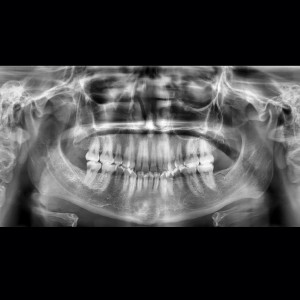

SERVICIOS 2D

SIALOGRAFIA

• Glándulas parótidas y sub maxilares